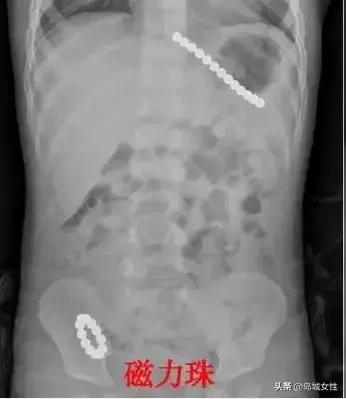

拍片显示

6颗圆珠连成串

停留在孩子的小肠和大肠中

更可怕的是

这几颗珠子竟然有磁性

观察了一天

孩子没法自主排出……

它们还会互相吸引

吸在了一块

由于肠管会自动收缩

在这过程中

异物移动可能穿刺肠壁

于是医生赶紧手术

珠子才被顺利取出

家长这才松了一口气